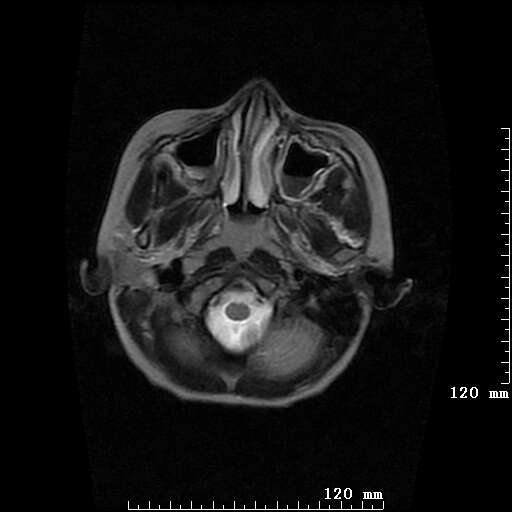

女,7岁,三岁才说话、走路。现智力尚可,走路不稳。临床怀疑大脑发育不全。

考虑 脑白质发育不良

脑折质变薄,双侧侧脑室稍扩张,支持考虑脑折质发育不良

考虑胼胝体发育不全,髓鞘形成不良。

支持考虑胼胝体发育不全,髓鞘形成不良。

脑裂畸形伴灰质异位

侧脑室周围白质数量减少,侧脑室不对称性扩大,左侧侧脑室后角呈方形改变,脑沟加深,结合临床考虑脑室周围白质软化症(pvl)。期待结果!